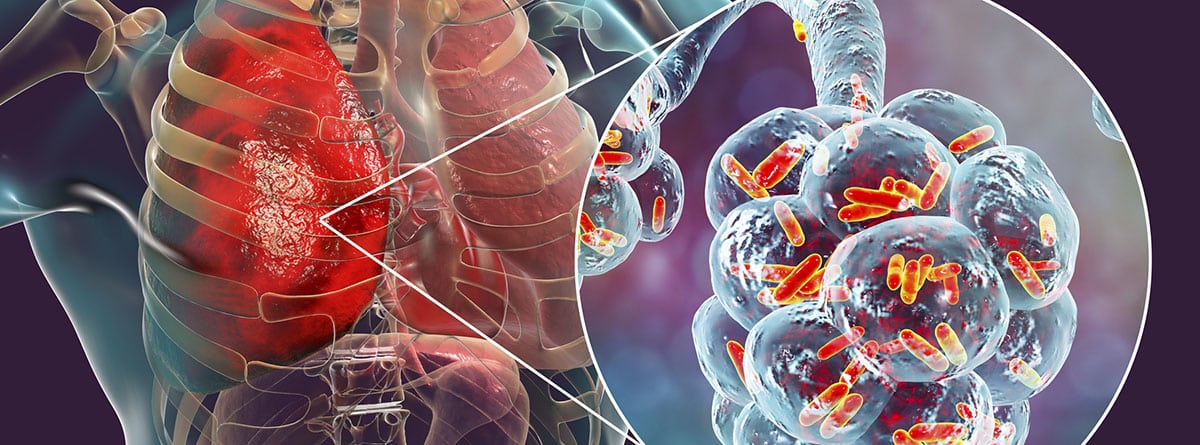

Глобальное бремя болезней: Инфографика и статистика